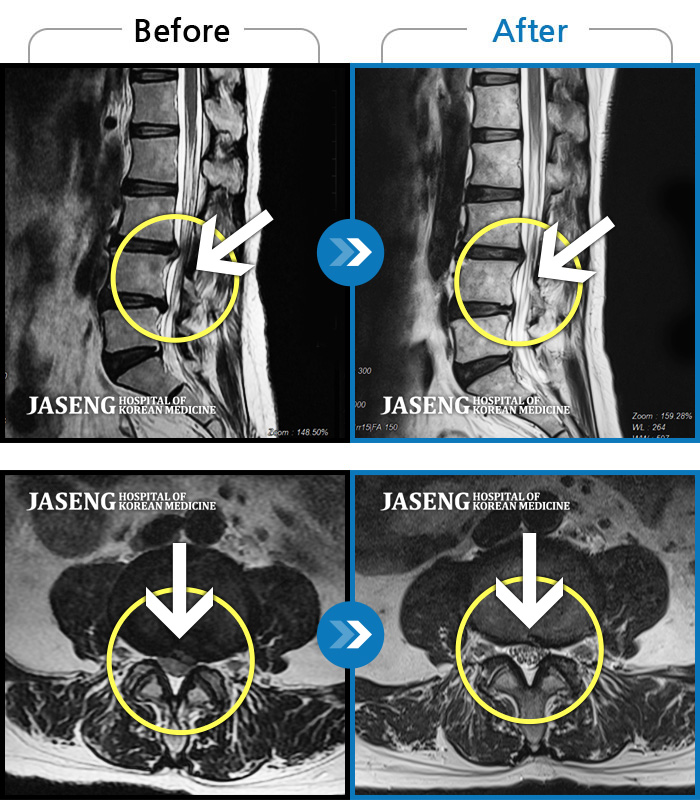

MRI ũ ʸ Ȯϼ.